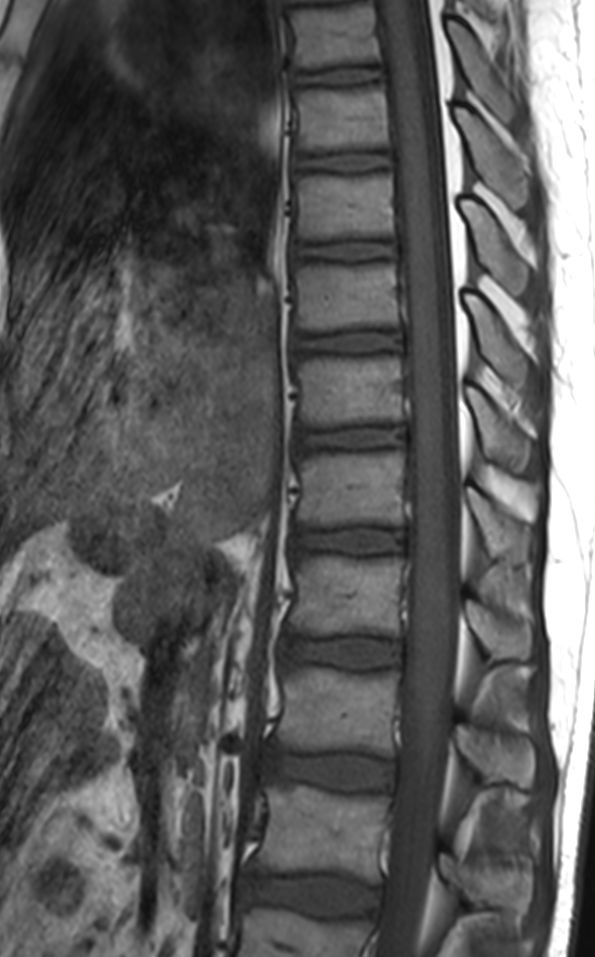

Sagittal T1w TSE (T-Spine)